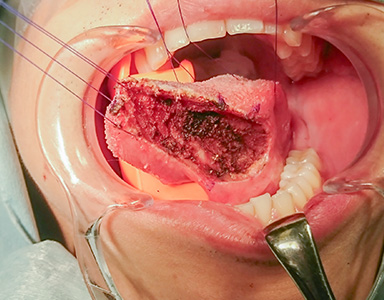

早期舌がんの治療(手術)の流れ

切除後の状態